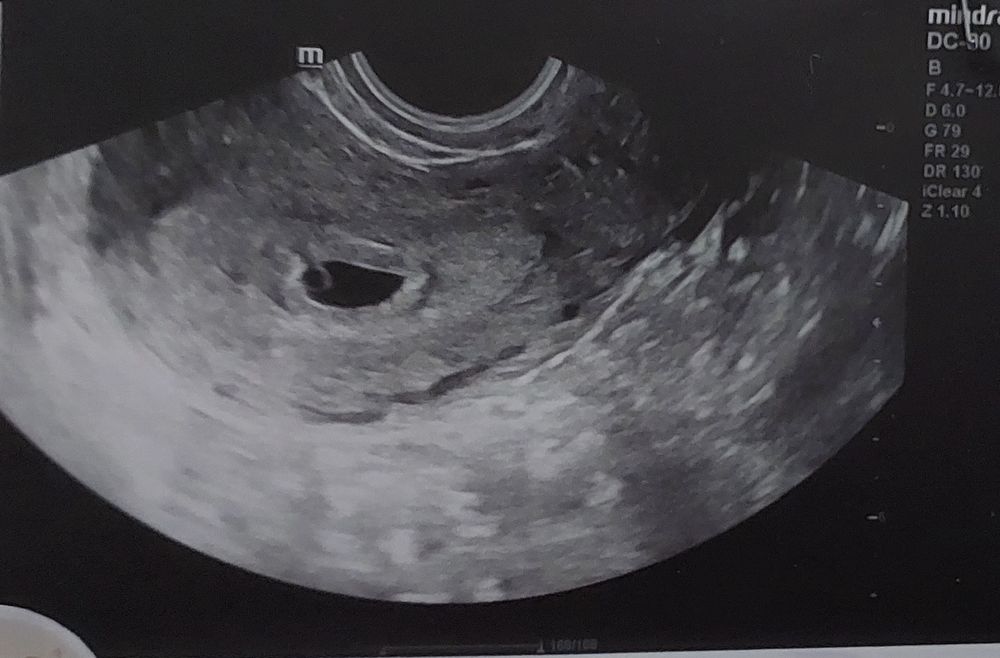

Плохое плодное яйцо